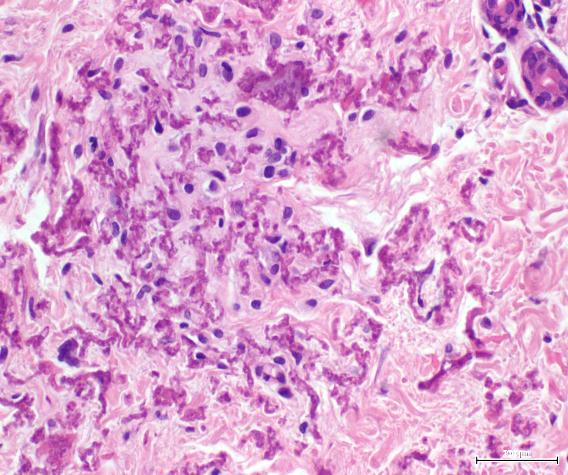

Se trata de un femenino de 35 años, quien inició enfermedad actual a los 15 años, caracterizada por la aparición pápulas amarillas con aspecto de piel de naranja, en cuello y axilas. En la biopsia de piel se observaron la presencia de fibras elásticas fragmentadas, engrosadas y basofílicas en dermis reticular. Los exámenes paraclínicos estaban dentro de los límites normales, ecocardiograma transtorácico sin alteraciones y la fundoscopia reveló estrías angioides. Nuestro caso se concluyó como Pseudoxantoma elástico, por cumplir con los todos los criterios mayores. Se indicó emolientes y fotoprotección; seguimiento por oftalmología, cardiología y genética.

The elastic pseudoxanthoma is a genetic disorder of the connective tissue that usually is transmitted in a dominant automatic recessive way. It is characterized by elastic fibers fragmentation and subsequent calcification affecting the dermis, blood vessels and the Bruch membrane of the retina. The low incidence of this pathology justifies the presentation of this case, in

which yellow papules lesions with location in the neck and armpits were evidenced, in addition to the angioid strias in the retina. The diagnosis was confirmed by skin biopsy and indicated symptomatic treatment with follow-up by cardiology, ophthalmology and by our service.